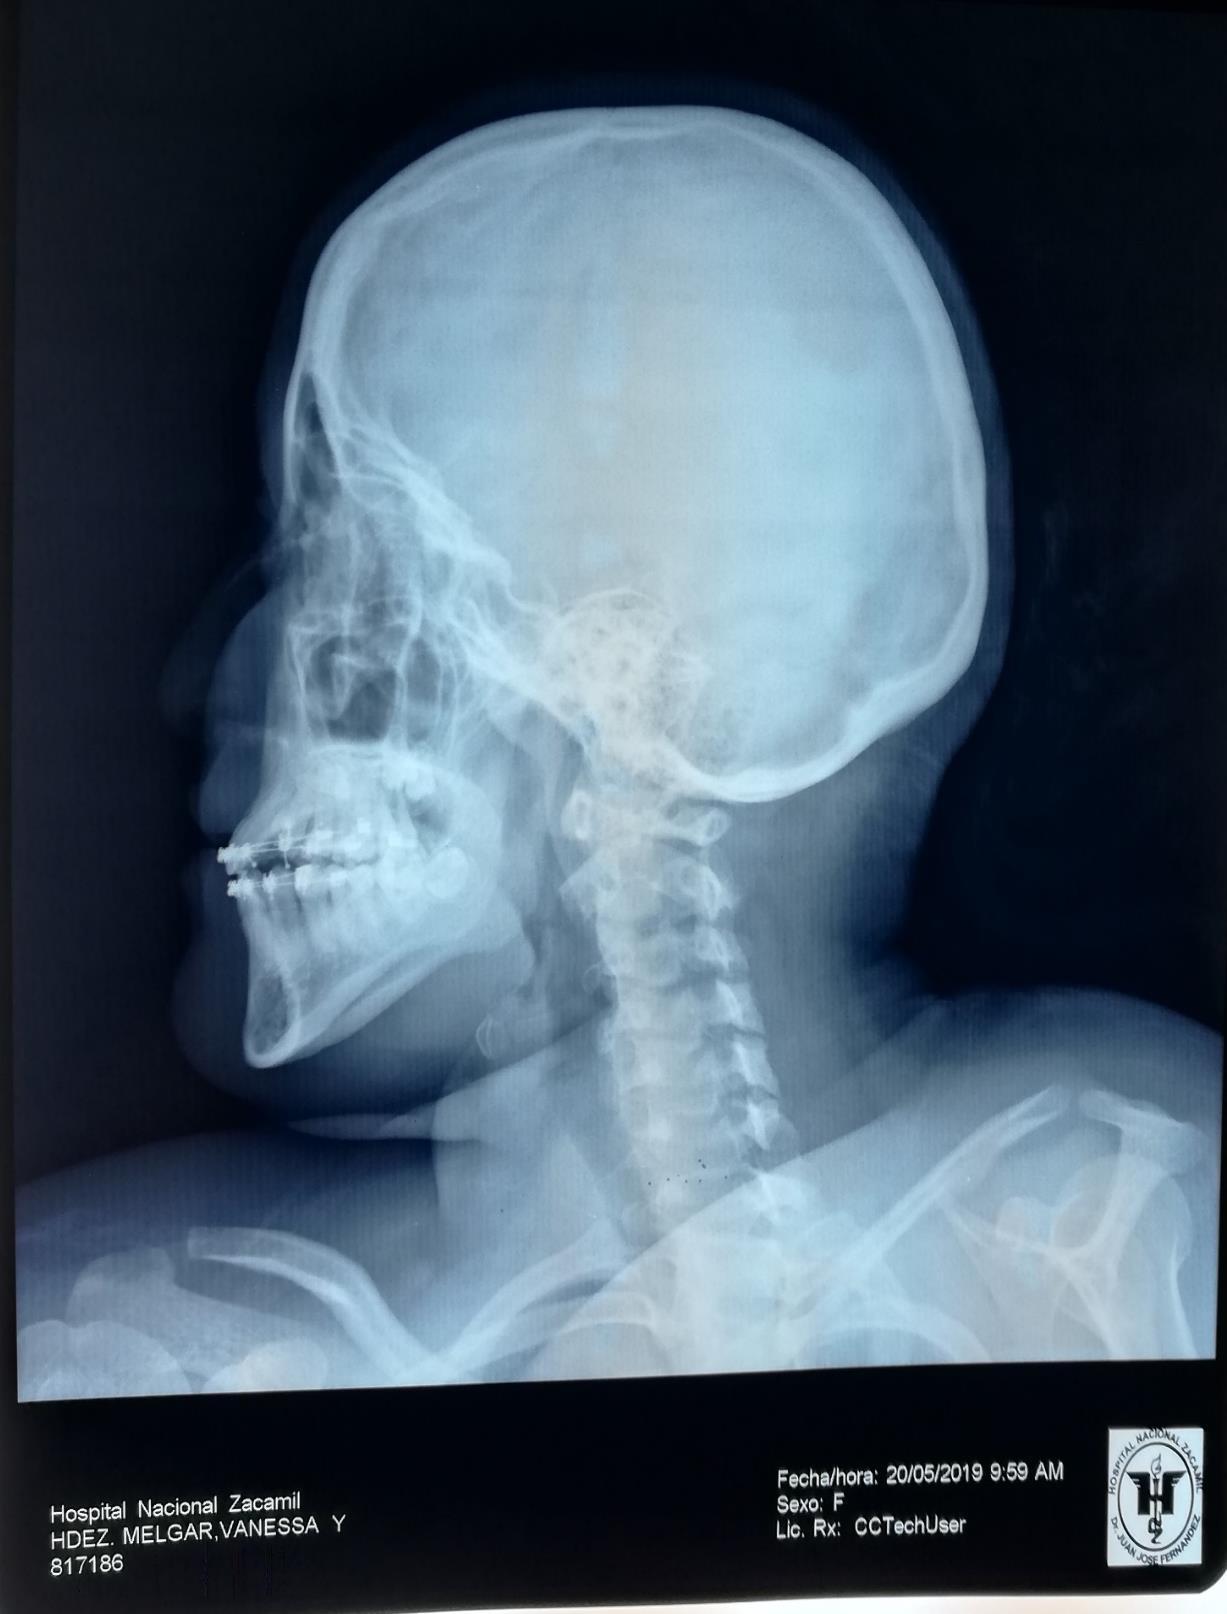

Paciente femenina de 25 años de edad, que se presenta con crecimiento de tejido blando en cuadrante I, a nivel de superficie de 15, 14,13,12,11. con protusión facial y compromiso de ala nasal del hemicara derecha.

Sistémicamente sana, exámenes no reportan anomalía y radiografías presentan lesión radiolucida en cuadrante I.

Se observa surco nasolabial derecho, comprometido (borrado), tercio medio de hemicara derecha, edematizado y protruido, asimetría facial marcada.

Lado afectado con forma leonina. Estima del paciente sumamente bajo, esquiva a la toma de fotografías.

Radiografía panorámica